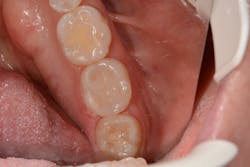

The lower left second molar was prepared for a class II composite restoration (figure 3). A sectional matrix band was placed and wedged. The preparation was etched, and adhesive was placed and cured. The VisCalor bulk was heated in the heating gun and then dispensed into the base of the box while in its flowable state. Note the complete adaptation of the material to the walls ofEditor's note: This article appeared in the November 2021 print edition of Dental Economics.